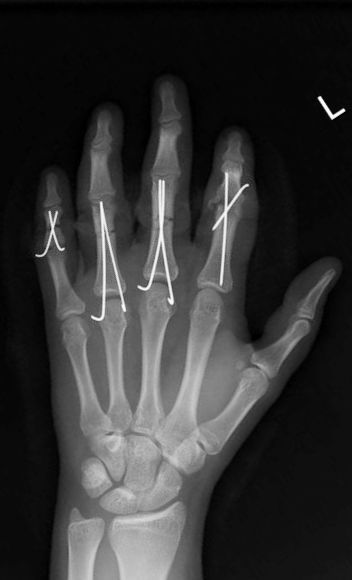

Hsu LP, Schwartz EG, Kalainov DM, Chen F, Makowiec RL. Complications of K-wire fixation in procedures involving the hand and wrist. J Hand Surg Am 2011;36(4):610-6.

Gillis JA, Lalonde J, Alagar D, Azzi A, Lalonde DH. K-wire fixation of closed hand fractures outside the main operating room does not increase infections. Plast Reconstr Surg Glob Open 2022;10(11):e4679.

Abul A, Karam M, Al-Shammari S, Giannoudis P, Pandit H, Nisar S. Peri-operative antibiotic prophylaxis in K-wire fixation: a systematic review and meta-analysis. Indian J Orthop 2023;57(7):1000-7.